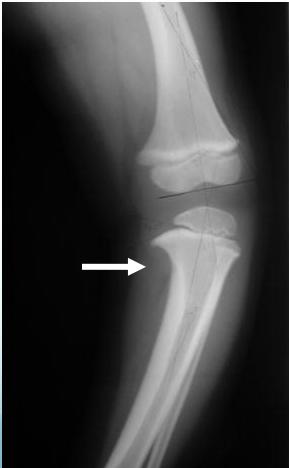

Indications: X-ray when severe or possibly pathologic

Recommended Views:

- Standing AP film: Long film (hips to ankles) with patellae directed forwards

Radiological Parameters to Assess:

- Medial Physeal Slope

- Femoral-Tibial Axis

Conditions to Look For:

Tibia vara (Blount’s disease)

Medial Physeal Slope

Femoral-Tibial Axis